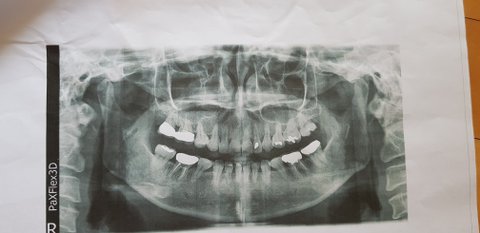

1, 3월27일 치아미백과 앞이사이 떨어진 레진을 붙이려고 동네치과에 감. 사진 찍어 보더만 상담실장 따라가서 설명들으라고.... 상담실장 왈 내이는 치아미백이 안되는 치아라고 함. 그리고 이럴때는 치아성형을 해야하며, 하고난뒤 만족감에 대하여서만 계속 권유 받음. 어떻게 하냐니 앞이 6개를 살짝갈고 씌우는 것이라 이야기들음. 망설이다 6×700.000=4.200.000 에 200.000만원 깍아준다하여 뭐에 씌인듯 계약함. 그리고 글씃이가 지갑을 통체로 잊어먹어서 돈을 한꺼번에 주지 못한다고 하니, 현금으로 나누어 내라고 하여, 남편에게 현금 100만원 받아서 줌

4, 4월20일 계속적인 신경치료와 앞이 다듬는 과정중, 보지 못했던 내 앞이 6개를 얼핏보고 충격받음

계약과 다르게 진행되고, 얼핏본 치아상태 내가잘못봤나 싶어서, 다른치과에 가서 의치를 빼고, 내 이빨을 보고 통곡을 했음. 앞이 6개가 쌀알갱이 처럼 남기고 다 깎였음. 그리고 내가하는 것이 무엇인지 정확하게 설명들음. 너무 어이없고, 사기 당했다는 생각에 치과로 전화를 함. 상담실장이 전화받아서 이때까지 이야기 한거랑 전혀다른 이야기를 들음. 내 앞이 6개가 모두 레진으로 덮여 있어서 다 갈아내야 했고, 가격이 다른치과와 너무 다르다고 항의한 나에게, 자기치과는 고 퀄티의 기술을 지니고 있어서 하고난뒤 가격에 비하여 만족할것이라고만 답변하며, 앞이는 부르는게 값이라는 말만 들음, 그리고 23일 예약도 잡혀있으니 그날와서 이아기 하자고 해서 알았다고 함